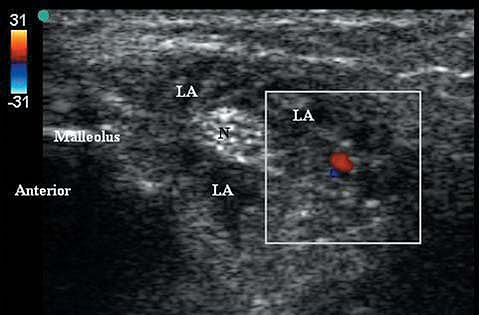

Sterile prep of the skin. A 13-MHz linear transducer is placed

posterior to the medial malleolus. The needle is placed anterior to the

probe in the longitudinal plane at an angle which is nearly tangential

to the skin. The needle is advanced with a current of 0.5 mA until

plantar flexion of the toes is elicited or until a paresthesia is

obtained. Injection of 3 to 5 mL of local anesthetic should surround

the nerve with a block hypoechoic ring (Fig. 42-4).

Figure 42-4.

Sonogram (with color Doppler indicating arterial pulse) demonstrating local anesthetic spread surrounding the posterior tibial nerve. N, posterior tibial nerve; LA, local anesthetic. |